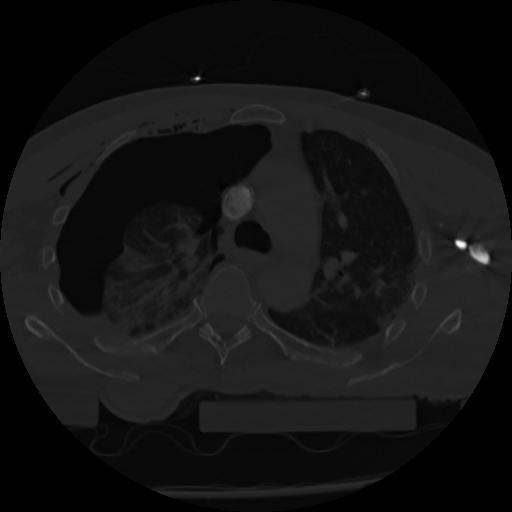

22 ANGIO,CE,Vol,0.5,ANGIO,,